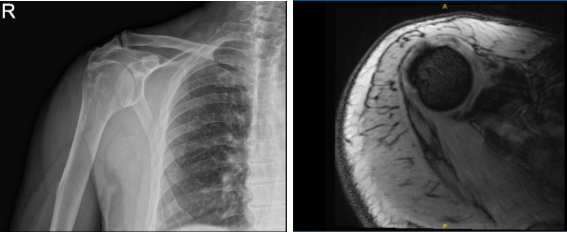

X-ray of my right shoulder were presented. Right shoulder showed calcific tendinitis. Narrowing of the glenohumeral joint as well as the acromiohumeral space. Degenerative changes of the acromioclavicular joint. MRI of the right shoulder recommended.

MRI results showed a significant reason for pain- Infraspinatus calcific tendinitis. Rotator cuff tendinosis and a moderate partial-thickness bursal surface tear of the supraspinatus tendon with intermixed attenuation tissue.

Mild partial-thickness articular surface tear of the subscapularis tendon. Moderate AC joint arthrosis and focal tear of the superior labrum at the chondrolabral junction were also found.

MRI X-ray of right shoulder